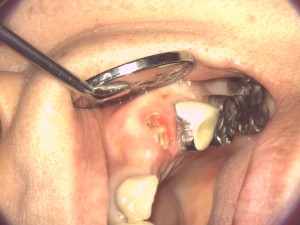

歯肉にメスを入れて剥離して骨を露出させます。

ピエゾサージェリー(超音波)で骨を削ります。

例えば、家の周りの土砂の部分を削ると地下が現れます。これと同様に歯の周りの骨を削ると歯の根っこが現れてここに被せものの辺縁を設定します。